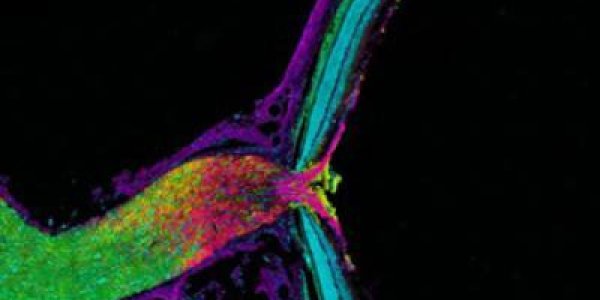

Transmitophagy?

Some basic biology may need revising. It's broadly assumed that cells degrade and recycle their own old or damaged organelles, but researchers writing in PNAS say that some neurons transfer unwanted…